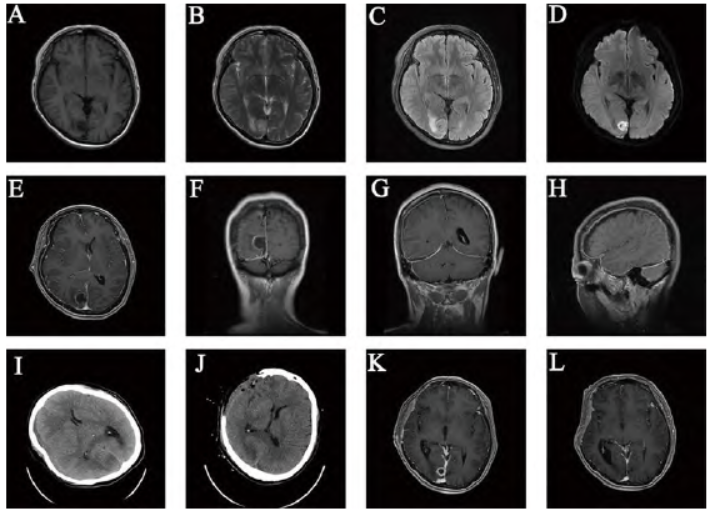

腰椎穿刺术后1 h,病情突然加重,嗜睡、双侧瞳孔直径不等大,急查血常规显示白细胞计数24.03×109/L。复查MRI显示右侧枕叶脑脓肿伴硬膜下积脓(图1E~H),复查头部CT(图1I)显示右侧硬膜下积脓,中线移位明显,脑疝

术后复查CT显示中线回位(图1J)。脓液涂片

4周。最终诊断:枕叶脑脓肿破溃、急性硬膜下积脓、脑疝。出院1个月复查,左侧肌力4级,右侧肌力5级;头部MRI显示枕叶脓肿缩小(图1K)。出院4个月复查,四肢肌力5级;头部MRI显示枕叶脓肿消失(图1L)。

图1 腰椎穿刺术后脑脓肿破裂致急性硬膜下积脓手术前后头部CT、MRI影像。A-D. 入院头部MRI显示右侧枕叶结节状长T1、长T2信号影,DWI呈高信号,压水像周围可见水肿

;E-H. 腰椎穿刺术后头部增强MRI显示右侧枕叶脓肿,环形强化,内与硬膜下腔相通,右侧小脑幕上、额颞顶枕部硬膜下腔增宽,中线结构左移;I. 腰椎穿刺术后头部CT显示右侧颅骨内板下等低密度影,中线结构左移,侧脑室受压,考虑脑疝形成;J. 急诊去骨瓣减压术后头部CT显示中线结构复位;K. 去骨瓣减压术后1个月复查头部MRI显示枕叶脓肿环形强化,体积明显减小;L. 去骨瓣减压术后4个月复查头部MRI显示枕叶脓肿消失